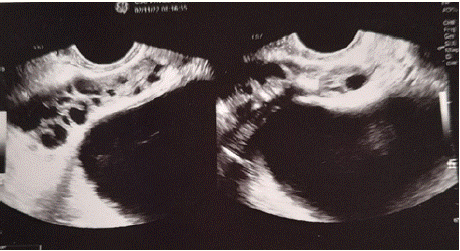

A case of adult, 120 kg, age 60 years old, diabetes type II controlled, hystory of recurrent prostatitis ( more then 20 year, every 3 month but also more frequent). Normal flux if not congested, light uretral restriction confirmed by retrograd uretroghraphy, abnormal urinary fluxumetry. Ecographic prostate: microcalcification present, and seminal vescicle volume increased.

Urologic inspection: normal volume (Figure 12).

Figure 12: Transrectal prostatic echography: seminal vescicle important

dilatation.